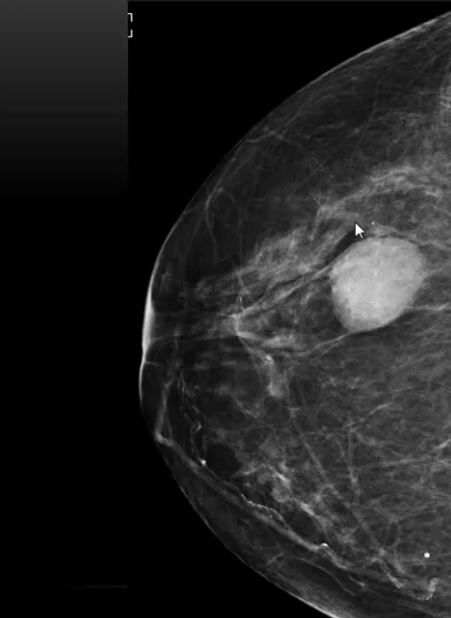

What is this an image of?

A mass